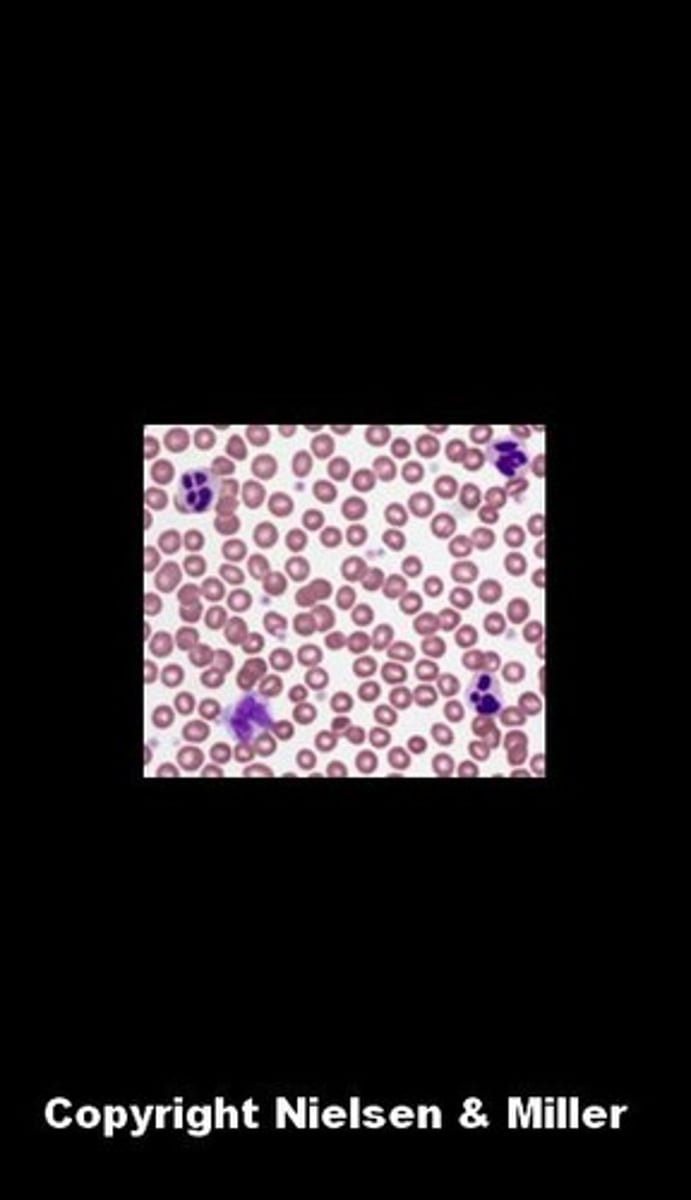

blood connective tissue